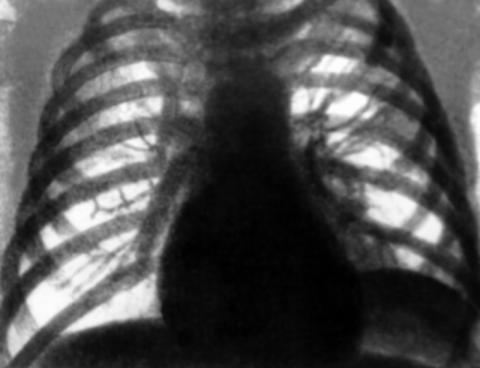

При осмотре отмечаются некоторое расширение и выбухание межреберных промежутков. Нарастающий объем жидкости оттесняет легкое кпереди и вверх, вследствие чего слой жидкости сзади становится более толстым, что при перкуссии очерчивает верхний край жидкости в виде линии Дамуазо, верхняя точка которой приходится на лопаточную линию. Над выпотом определяется тупой перкуторный звук. Важным клиническим симптомом наличия свободной жидкости является неподвижность нижнего легочного края. При значительных выпотах границы относительной сердечной тупости смещаются в здоровую сторону. Границу относительной сердечной тупости на стороне выпота можно установить с помощью метода аускультативной перкуссии. При аускультации над выпотом определяется ослабление или исчезновение дыхательных шумов, голосового дрожания и бронхофонии, однако при плевральных сращениях в зоне выпота эти симптомы могут отсутствовать. Непосредственно над выпотом может выслушиваться бронхиальное дыхание.

Важным признаком ПВ является смещение органов средостения. При парапневмонических плевритах средостение смещается в здоровую сторону. При выпоте, который сочетается с ателектазом или с пневмоциррозом, – в сторону поражения. Смещение органов средостения в сторону поражения при вторичном опухолевом плеврите при раке легкого является неблагоприятным прогностическим признаком.